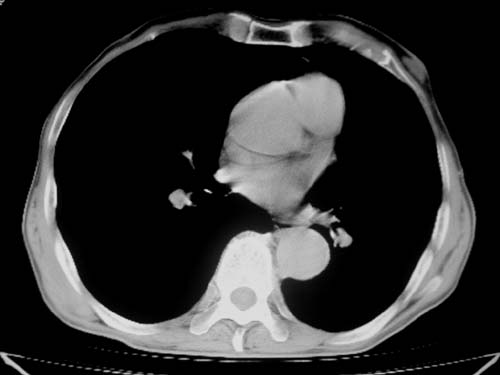

标题: CT19736:男,76岁,咳嗽,胸痛 [打印本页]

标题: CT19736:男,76岁,咳嗽,胸痛

支持左上肺周围型肺癌性并空洞形成伴胸椎转移。

支持 左上肺周围型肺癌性并癌性空洞形成伴胸椎转移。

左上肺周围型肺癌性并空洞形成伴胸椎转移。支持

考虑癌性空洞并胸椎转移。

左上肺癌性空洞伴胸椎转移。